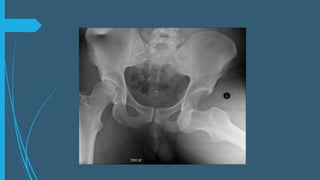

Valoración de imagen

Proyección anteroposterior

de la pelvis

En una AP: observar la línea

de Shenton continua y

regular.

Hay que valorar el cuello del

fémur para descartar una

fractura antes de realizar

maniobras de reducción .

La proyección oblicuas a 45°

(Judet) son útiles para valorar

si hay frag. Osteocondrales ,

el acetábulo y fx de femur.

Tras la reducción se toma

una TC.

La RM útil para valoración

del cartilago articular y

vascularización